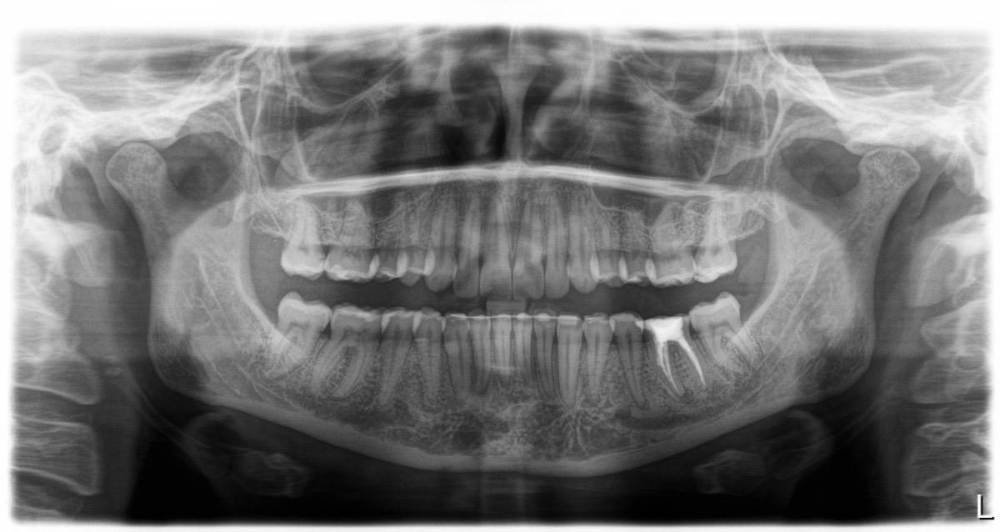

Я сняла брекеты 3,5 года назад. На нижней челюсти был ретейнер, на верхней нет.  Зубы на верхней челюсти сместились, на нижней остались в прежних позициях и зуб двойка снизу справа стал первой точкой контакта челюстей и оказался под большой нагрузкой. Таков был единственый вердикт стоматологов, объясняющий почему эта двойка болит на холодное и горячее. Чтобы избавиться от боли без эндолечения я решила пройти ортодонтическое лечение заново. Выбор пал на Инвизилайн, но несмотря на уже оплаченый план лечения меня терзают сомнения могу ли я с зубом в таком состоянии начинать лечение. Спрашивала можно ли начинать лечить отдельно верх, потом когда уйдет нагрузка с зуба подключить низ. Ортодонт сказала нет, инвизилайн начинают одновременно верх и низ. Вопрос можно ли начинать лечение в таком состоянии двойки? И есть ли альтернативы помочь ситуации без ортодонтии и эндодонтии, мне предлагали подпилить зуб, но я не уверена нормальный ли это выход, не вызовет ли это больших проблем с чувствительностью, не спровоцирует ли отмирание нерва? Состояние 35,36 прошу не комментировать, снимку полгода, с тех пор ситуация с ними изменилась.